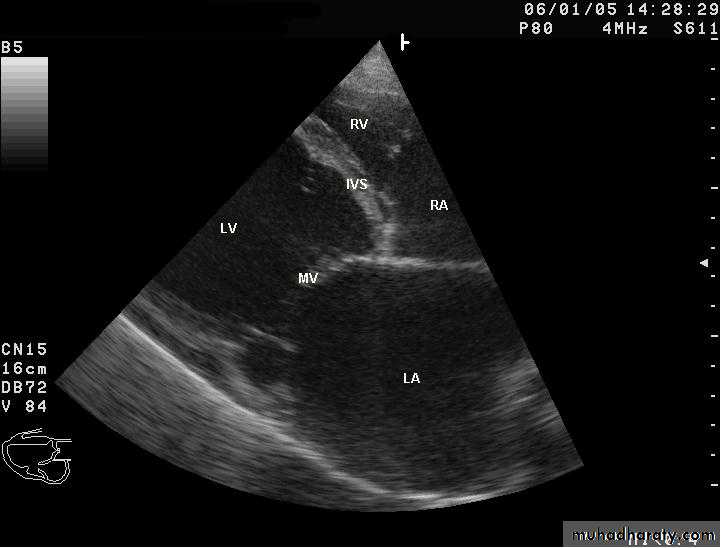

3-Conduction defectC- Echocardiography :

1- LV dilatation2-Mitral and tricuspid regurgitation

3-Reduce ejection fraction -systolic dysfunction

4- Other

#Echocardiography may reveal left ventricular dysfunction that is sometimes regional (due to focal myocarditis),